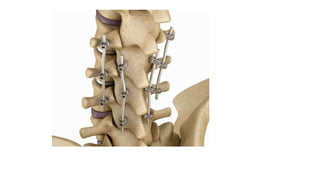

Surgery for deformity correction

Any deformity anywhere in body need to be corrected

permanently or to great extent by means of

soft tissue release erasing muscles or ligaments to achieve

correction

osteotomy cutting the deformed bone to achieve correction

Fusion of joint or orthrodesis to rtain it in corrected position

After achieving desired correction there is usually need to retain it

externally by means of calipers or braces, or internally by

appropriate implants